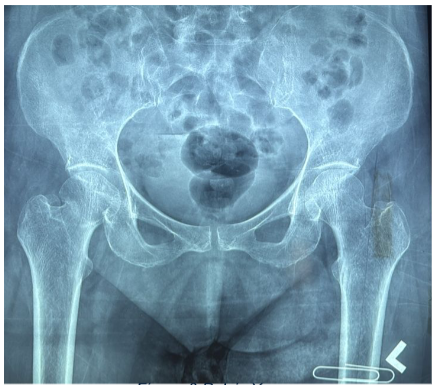

Pelvis X-ray: Right neck of femur fracture